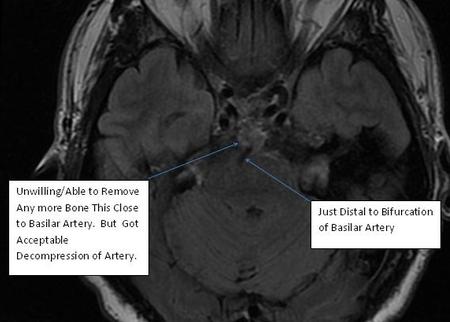

For more medical people, a small fragment of bone was left adjacent to the basilar artery. It was too tough to get to and not worth the risk as determined by Dr. Gardner.

Physicians at UPMC in Pittsburgh developed new technique around 2010. Using a small endoscope, through the nose, then a small catheter through the back of the nasopharynx ( nose/mouth ) they removed ( via tiny drill ) most of C1 and C2. Quite risky being that close to brain stem. No small complications, sort of an all or nothing thing. This is me 2 weeks post surgery.